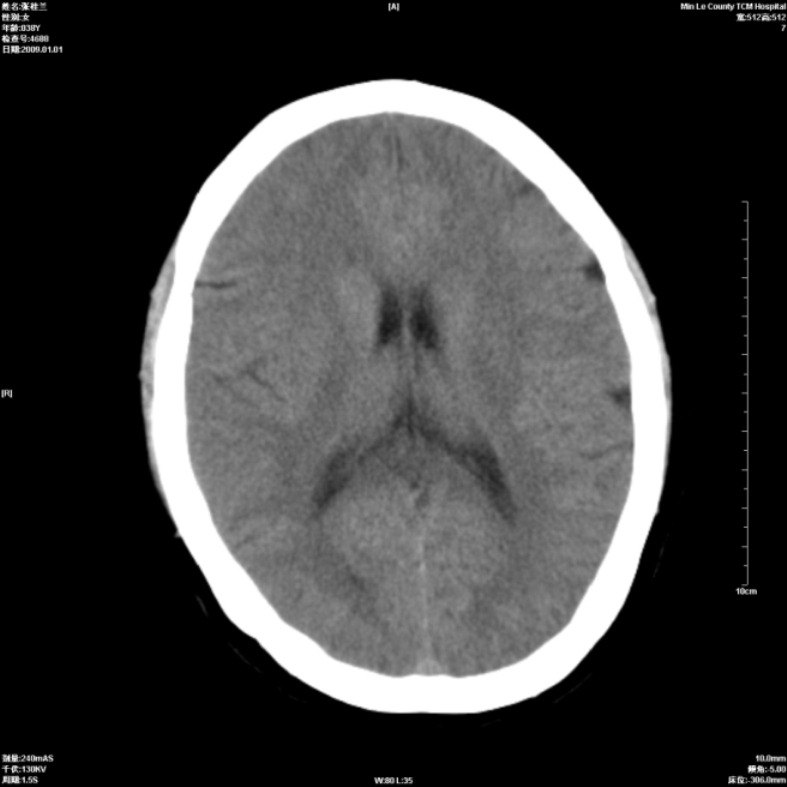

以下是引用hhcckk在2009-1-1 15:56:00的发言:[br]癫痫的原因一般与四种因素有关:[br] 1.遗传因素在一些有癫痫病史或有先天性中枢神经系统或心脏畸形的病人家族中容易出现癫痫;[br] 2.脑损害与脑损伤在胚胎发育中受到病毒感染放射线照射或其它原因引起的胚胎发育不良可以引起癫痫;胎儿生产过程中产伤也是引起癫痫的一个主要原因;颅脑外伤也可引起癫痫;[br] 3.颅脑其它疾病脑肿瘤脑血管病颅内感染等;[br] 4.环境因素;男性病人较女性病人稍多农村发病率高于城市另外发热精神刺激等也是癫痫发生的诱因。[br][br]此病例在额叶有片状低密度灶,无明显占位与负占位效应,结合癫痫的常见原因考虑[br]1、外伤后软化灶,包括产伤,可以结合病史鉴别[br]2、血管畸形的窃血现象形成的萎缩?

以下是引用xulianj在2009-1-1 16:09:00的发言:[br]支持:蛛网膜粒囊肿!